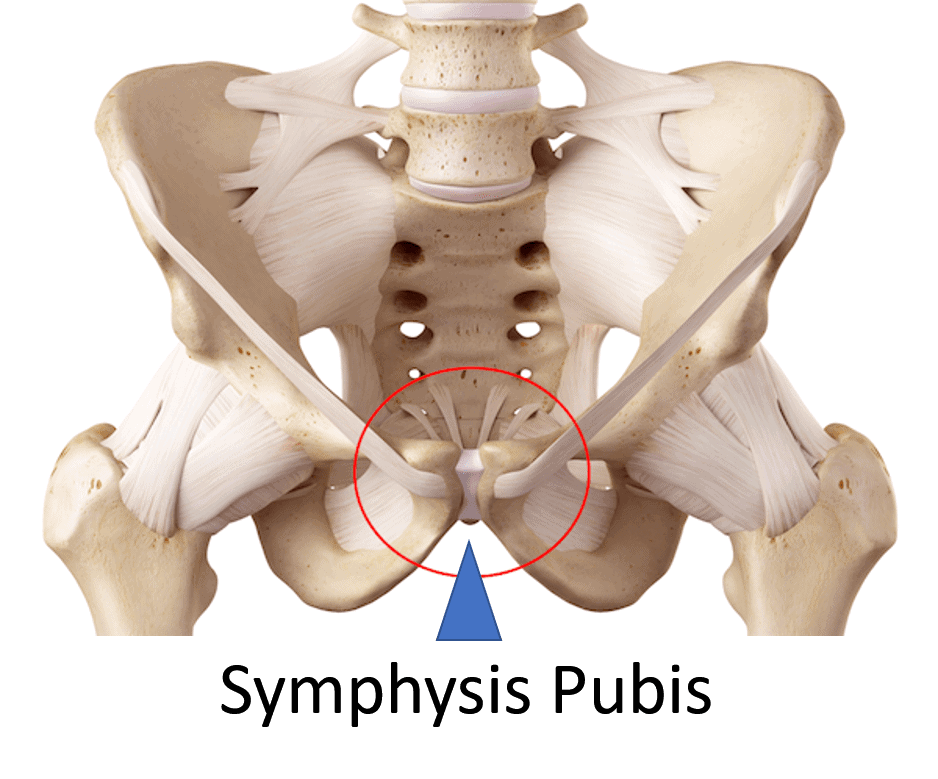

To better understand osteitis pubis, it’s helpful to first explore the anatomy of the pelvic ring and the symphysis pubis. The pelvis is a ring-shaped bony structure that plays a key role in supporting movement and stability in the lower body.

At the back, it connects through two sacroiliac (SI) joints, while at the front, it meets at the symphysis pubis. This interconnected arrangement of bones, joints, and soft tissues helps support body weight, contributes to movement, and provides protection for internal organs.

Taking a closer look at the pelvic ring and the symphysis pubis can offer helpful context for understanding osteitis pubis. The pelvic ring includes two sacroiliac joints at the rear and the symphysis pubis at the front, forming a closed structure that may influence lower body function and stability.

The symphysis pubis is a joint located at the front of the pelvis and is structured primarily for stability rather than mobility. Unlike highly mobile joints such as the knee or shoulder, it includes a fibrocartilaginous disc between the left and right pubic bones. This design may help the joint absorb stress and adapt to certain physical demands while supporting the overall stability of the pelvic region.